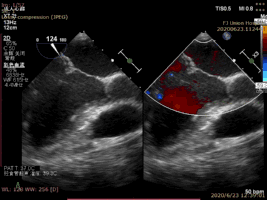

病例2術(shù)后二尖瓣反流為輕度